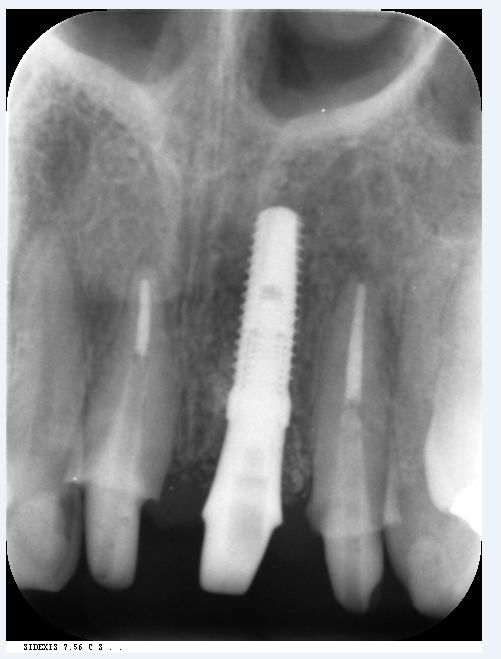

今日は前歯のインプラントの7年経過をみて頂きます。

この方はNさん、女性、7年前にインプラントを行いました。

当時左上1番の根っこが折れていました。

保存は不可能な状態でした。

初診時写真です。

治療に関しては抜歯と同時にインプラントを埋入し安定させました。